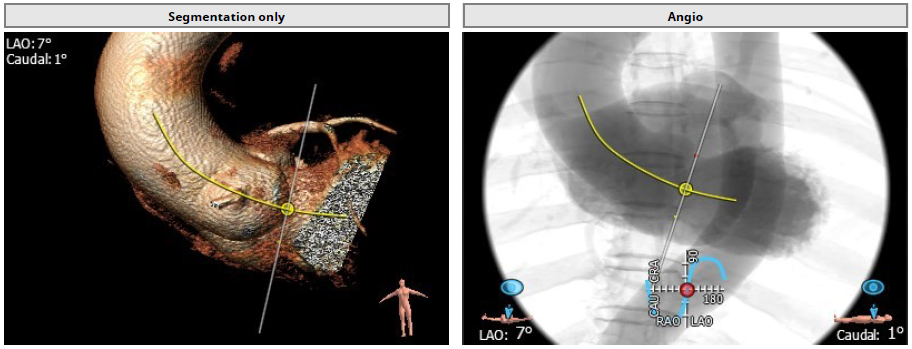

4.患者术中造影角度LAO:7°,CAU:1°。

术中造影角度LAO: 7°,Caudal: 1°

用经胸超声心动图确定心尖位置,并做好标记。常规肝素化,按照心尖标记,行第5、6 肋间左胸前外侧小切口,充分暴露心尖后将心包切开并悬吊,用3-0 Prolene 线加毛毡片完成荷包缝合。经股动脉植入6Fr鞘管,并插入猪尾造影导管至主动脉根部,造影确定主动脉瓣瓣环水平及两侧冠状动脉开口。

经心尖途径置入 J-Valve 瓣膜输送系统,在升主动脉部打开定位件,调整角度,轻轻向后牵拉输送器使定位件进入主动脉窦内。联合主动脉根部造影和食管超声观看定位件是否定位于窦底,形态随着心脏跳动而自然摆动即可。下降瓣膜至主动脉瓣环内,在主动脉瓣口释放瓣膜支架,此过程无需快速起搏。瓣膜成功释放后移除瓣膜输送系统。行主动脉根部造影及经食管超声检查,对瓣膜功能、位置情况进行术后即刻评估。确认位置良好、功能正常后,移除导丝及输送系统,并收紧心尖荷包缝线打结固定。

最后再次血管造影确认介入瓣膜位置稳定,活动良好,无瓣周漏,冠状动脉开口无阻塞。